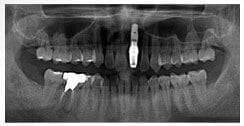

X 光片

術前X光片